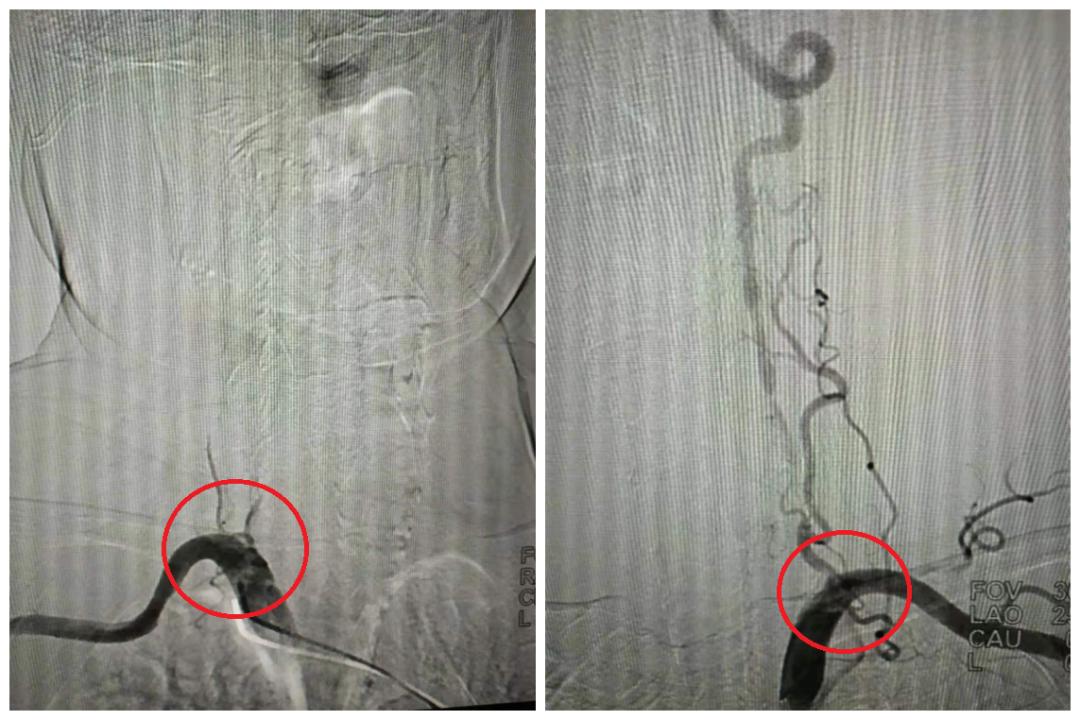

经过磁共振检查, 神经内科季新发主任 诊断:老人患有多发性脑梗死。进一步头颈部CTA检查,发现老人双侧椎动脉闭塞、颈动脉重度狭窄。

双侧椎动脉起始段闭塞(局部),右图含侧支代偿

双侧颈动脉C1段狭窄(局部)